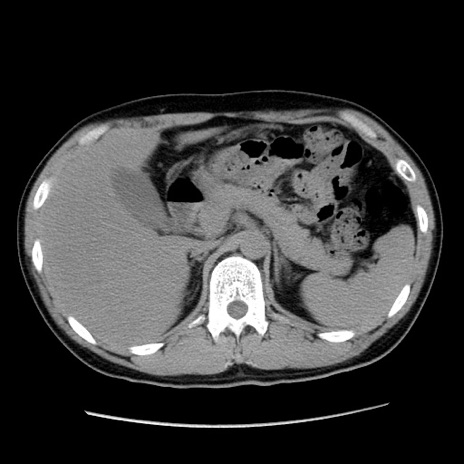

症例36(横断像)

【症例】20歳代 男性

【主訴】心窩部痛

【現病歴】今朝より上腹部痛あり。一旦軽快していたが再度出現したため救急要請。昨日夕に白身の魚を含む刺身を食べた。

【身体所見】BP 136/89mmHg、HR 74/min、BT 37.0℃、腹部:膨満、軟、心窩部に圧痛あり。反跳痛なし、筋性防御なし、腸雑音やや亢進あり。

【データ】WBC 17700、CRP 0.48